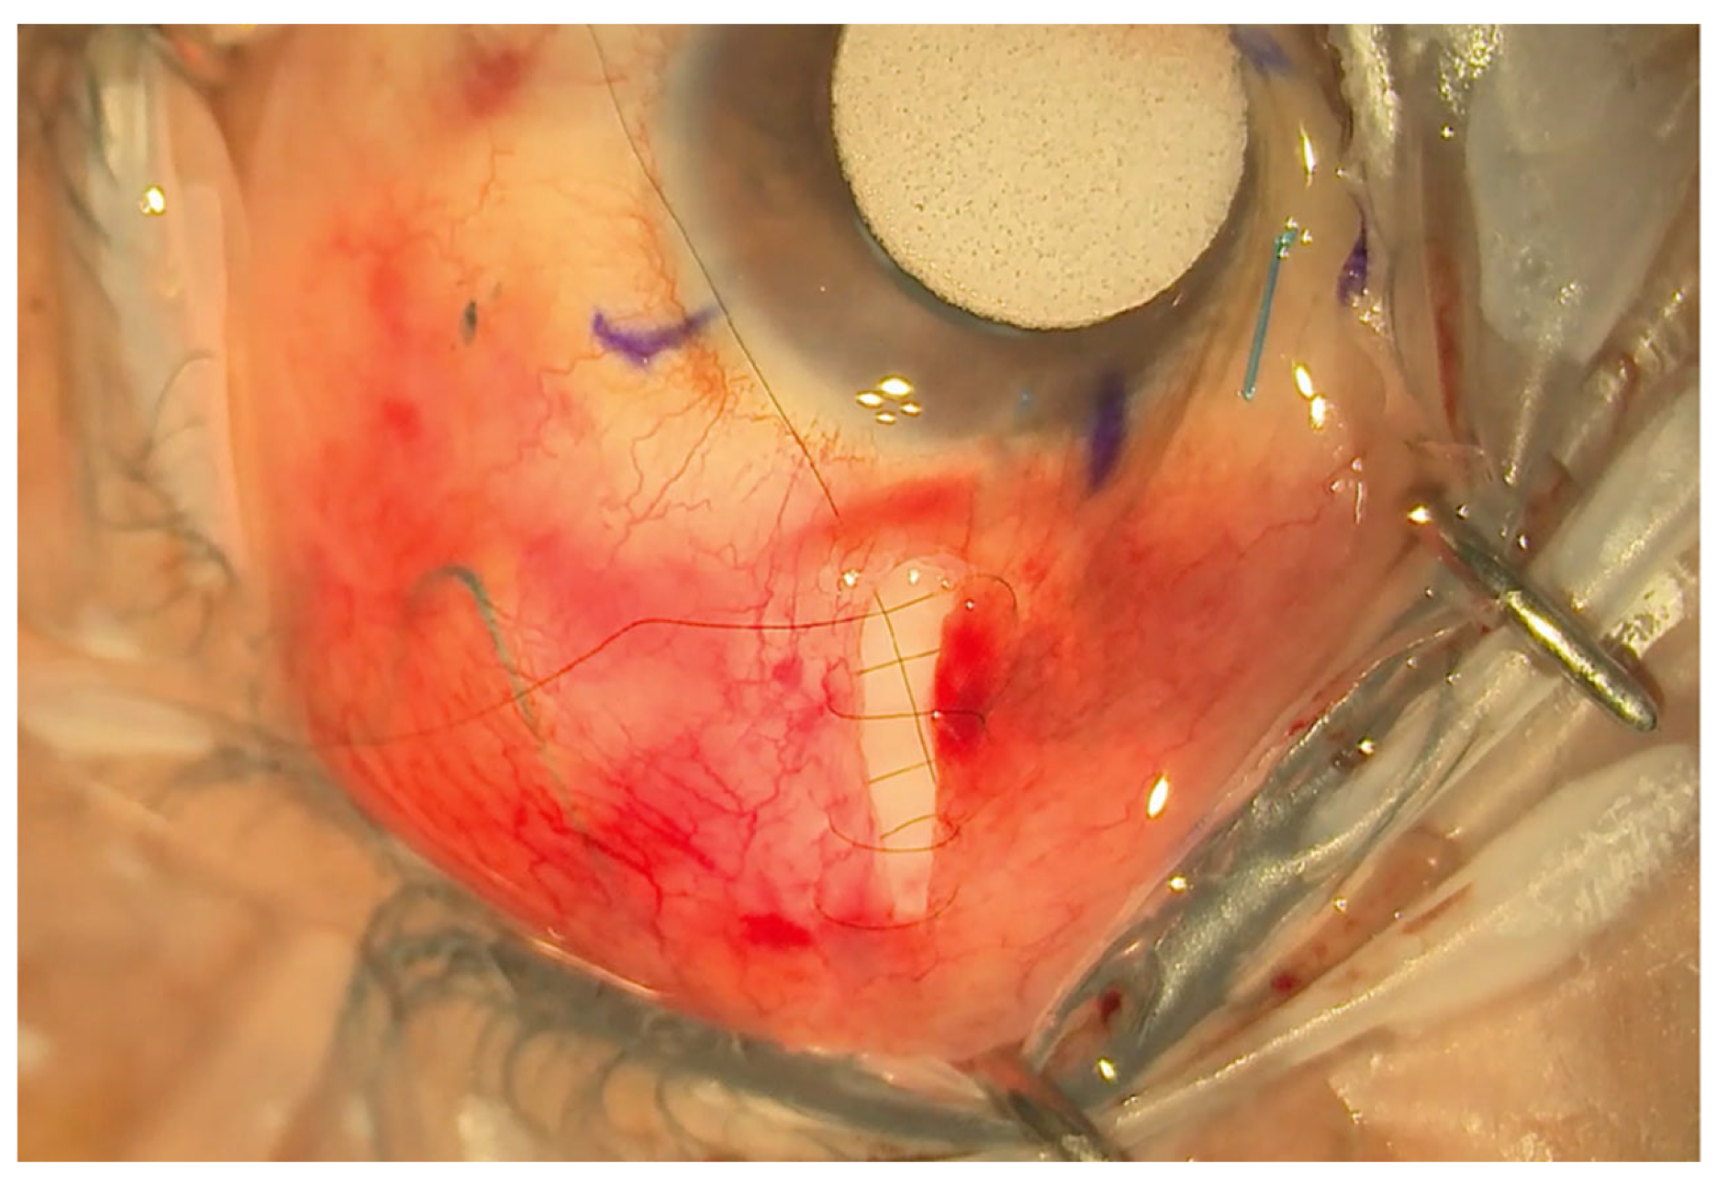

Figure 3.

Small radial incision closed with a shoelace suture.

The eyePlate-300 is then sutured via the two eyelets on the plate to the sclera with a 9/0 prolene suture. After trimming the tube to a bevel, the tube is inserted into the anterior chamber via a sclerostomy, which is made 2 mm from the limbus with a 25-gauge needle. The tube is then sutured to the sclera with a 9/0 prolene box suture. An occluding 7/0 vicryl suture is tied around the tube to help prevent early hypotony.

A double layer of Tutoplast allograft tissue (Innovative Ophthalmic Products, Costa Mesa, CA, USA) is glued with Tisseel fibrin sealant (Baxter AG, Vienna, Austria). The 4/0 prolene stent suture end is tucked in the inferior fornix under the conjunctiva to facilitate ease of removal later in the outpatient setting. The end of the 4/0 prolene can be cauterised into a small bulb so it rests better under the conjunctiva and does not protrude through it. The smaller radial peritomy is then closed with Tisseel fibrin sealant glue and sutured with a 10/0 nylon suture. (Figure 3). To complete the surgery, a subconjunctival steroid and antibiotic are administered as well as an orbital floor 40 mg injection of methylprednisolone. See Figure 4 for a one-week post-operative outcome.